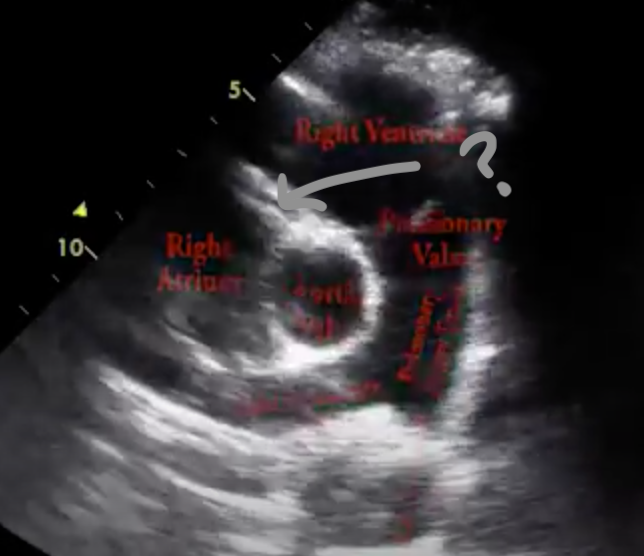

Q

The arrow (gray one) in this image is pointing to the:

A

Left main coronary artery

*the image demonstrates the left coronary artery originating from the left coronary cusp